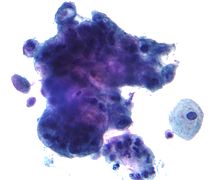

Cancer screening programs serve as effective sources of secondary prevention. The Mayo Clinic, Johns Hopkins, and Memorial Sloan-Kettering hospitals conducted annual x-ray screenings and sputum cytology tests and found that lung cancer was detected at higher rates, earlier stages, and had more favorable treatment outcomes, which supports widespread investment in such programs.[46]

Cervical cancer

Cervical cancer ranks among the top three most common cancers among women in Latin America, sub-Saharan Africa, and parts of Asia. Cervical cytology screening aims to detect abnormal lesions in the cervix so that women can undergo treatment prior to the development of cancer. Given that high quality screening and follow-up care has been shown to reduce cervical cancer rates by up to 80%, most developed countries now encourage sexually active women to undergo a Pap test every 3–5 years. Finland and Iceland have developed effective organized programs with routine monitoring and have managed to significantly reduce cervical cancer mortality while using fewer resources than unorganized, opportunistic programs such as those in the United States or Canada.[56]

In developing nations in Latin America, such as Chile, Colombia, Costa Rica, and Cuba, both public and privately organized programs have offered women routine cytological screening since the 1970s. However, these efforts have not resulted in a significant change in cervical cancer incidence or mortality in these nations. This is likely due to low quality, inefficient testing. However, Puerto Rico, which has offered early screening since the 1960s, has witnessed almost a 50% decline in cervical cancer incidence and almost a four-fold decrease in mortality between 1950 and 1990. Brazil, Peru, India, and several high-risk nations in sub-Saharan Africa which lack organized screening programs, have a high incidence of cervical cancer.[56]